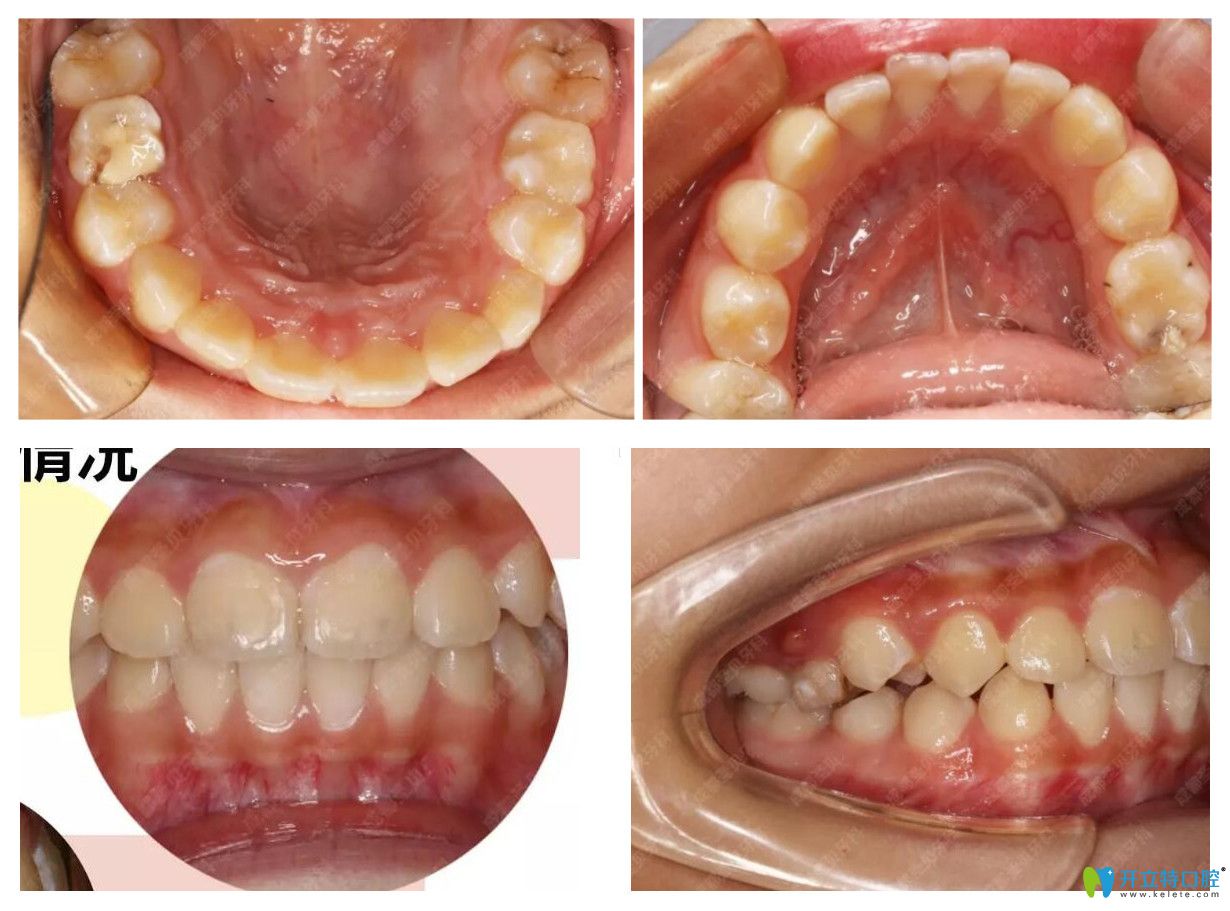

矯正后效果圖:

正畸后口腔照片:

矯正后口腔癥狀牙列排擠,牙縫不見了,微凸的上門牙得到了改善,反合的牙齒也恢復(fù)了正常位置,矯正前未曾萌出的恒牙現(xiàn)在也整齊的出現(xiàn)啦!